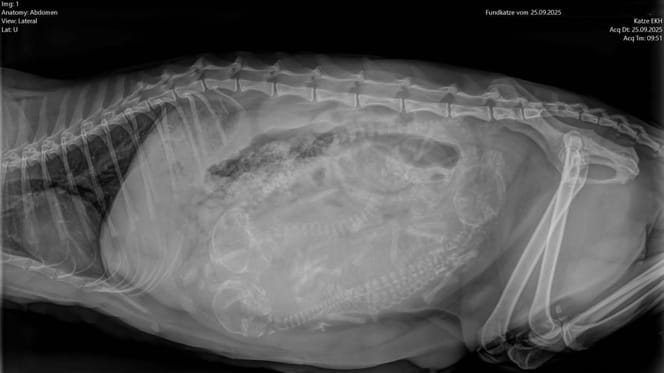

Radiografía de una gata preñada

Radiografía de una gata preñada.

© Tierheim Bochum / Facebook

Los huesos mostraban deformaciones evidentes, un signo típico de los scottish fold debido a una cría que provoca sufrimiento.

Las adorables orejas dobladas hacia adelante, típicas de los scotish fold —que muchas personas consideran encantadoras— son en realidad la consecuencia de una mutación genética que causa daños crónicos en huesos y articulaciones a lo largo de toda la vida del animal.